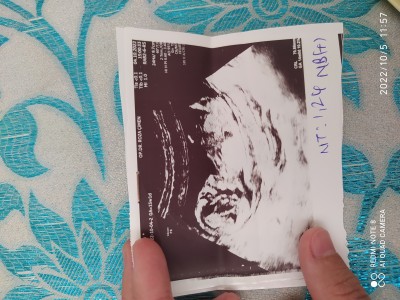

13+4 haftalık hamişim sadece teorilere göre tahmin yapabilen var mı anneler ❤️

Erkek gecdi icimden canım

Baska foto yokmu bu yanıltıcı durusu net değil erkek gecdi ama baska resim varsa bakim

Erkek bebişim olacakmış;))

Hayırlısı gülüm ama içimden hep kız gibi geliyor ya

İcinden kız gectim. Suana kadar hic bir cinsiyet tahminimde yanilmadim :) sağlıkla gelsin inşallah